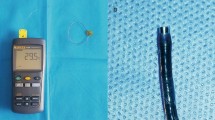

Thermocouple and data logger

The thermocouple used was SE001 from (Pico Technologies, Cambridgeshire, UK). It has an exposed junction and 0.3-mm twisted pair conductor and fiberglass insulated. It has a tip diameter of 1.5 mm and can record a temperature range from − 60 °C to + 350 °C (Fig. 1). The thermocouple was connected to a data logger (TC08, Pico Technologies, Cambridgeshire, UK) for real-time temperature measurements (Fig. 1). The data logger has 8 channels that can support all popular thermocouple types and can measure temperature from − 270 to + 1820 °C with high resolution and accuracy. It can record up to 10 measurements per second and comes with a USB cable for connecting with laptop. In this study the data acquisition rate was set at 1 count/s.